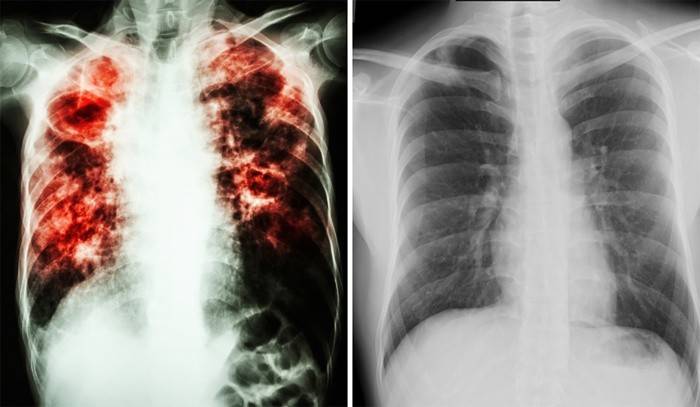

Como a tuberculose é transmitida e quais são seus sintomas? A doença pode ocorrer de duas formas: fechada ou aberta. Ambos os tipos de doença têm seus próprios sinais / sintomas. Mas não se esqueça de como a tuberculose é transmitida - ambas as formas são igualmente perigosas e se espalham por gotículas no ar. Os primeiros sintomas são muito enganadores e parecem com uma gripe comum. Se você não consultar um especialista a tempo, a doença se desenvolverá em um estágio complicado e levará à morte.

Esta é a forma mais perigosa de tuberculose que afeta os pulmões e o sistema respiratório. Ela tem os seguintes sintomas:

- Alta temperatura (37-38 graus).

- Tosse forte e prolongada.

- Dores no peito.

- Falta de apetite.

- Sonolência, letargia, fadiga.

- Perda de peso repentina.

- Tosse com expectoração ou sangue.

O principal perigo de uma forma aberta de tuberculose é um possível desfecho fatal se a doença não for tratada em tempo hábil. Em um estágio inicial, a doença é tratável com antibióticos. É necessário fazer um curso de reabilitação em um centro especial de pneumologia para proteger outras pessoas da doença. Embora a taxa de doença tenha diminuído em 40% desde os anos 90, o risco de pegá-la continua grande. Portanto, todas as pessoas simplesmente precisam saber como a tuberculose de tipo aberto é transmitida.